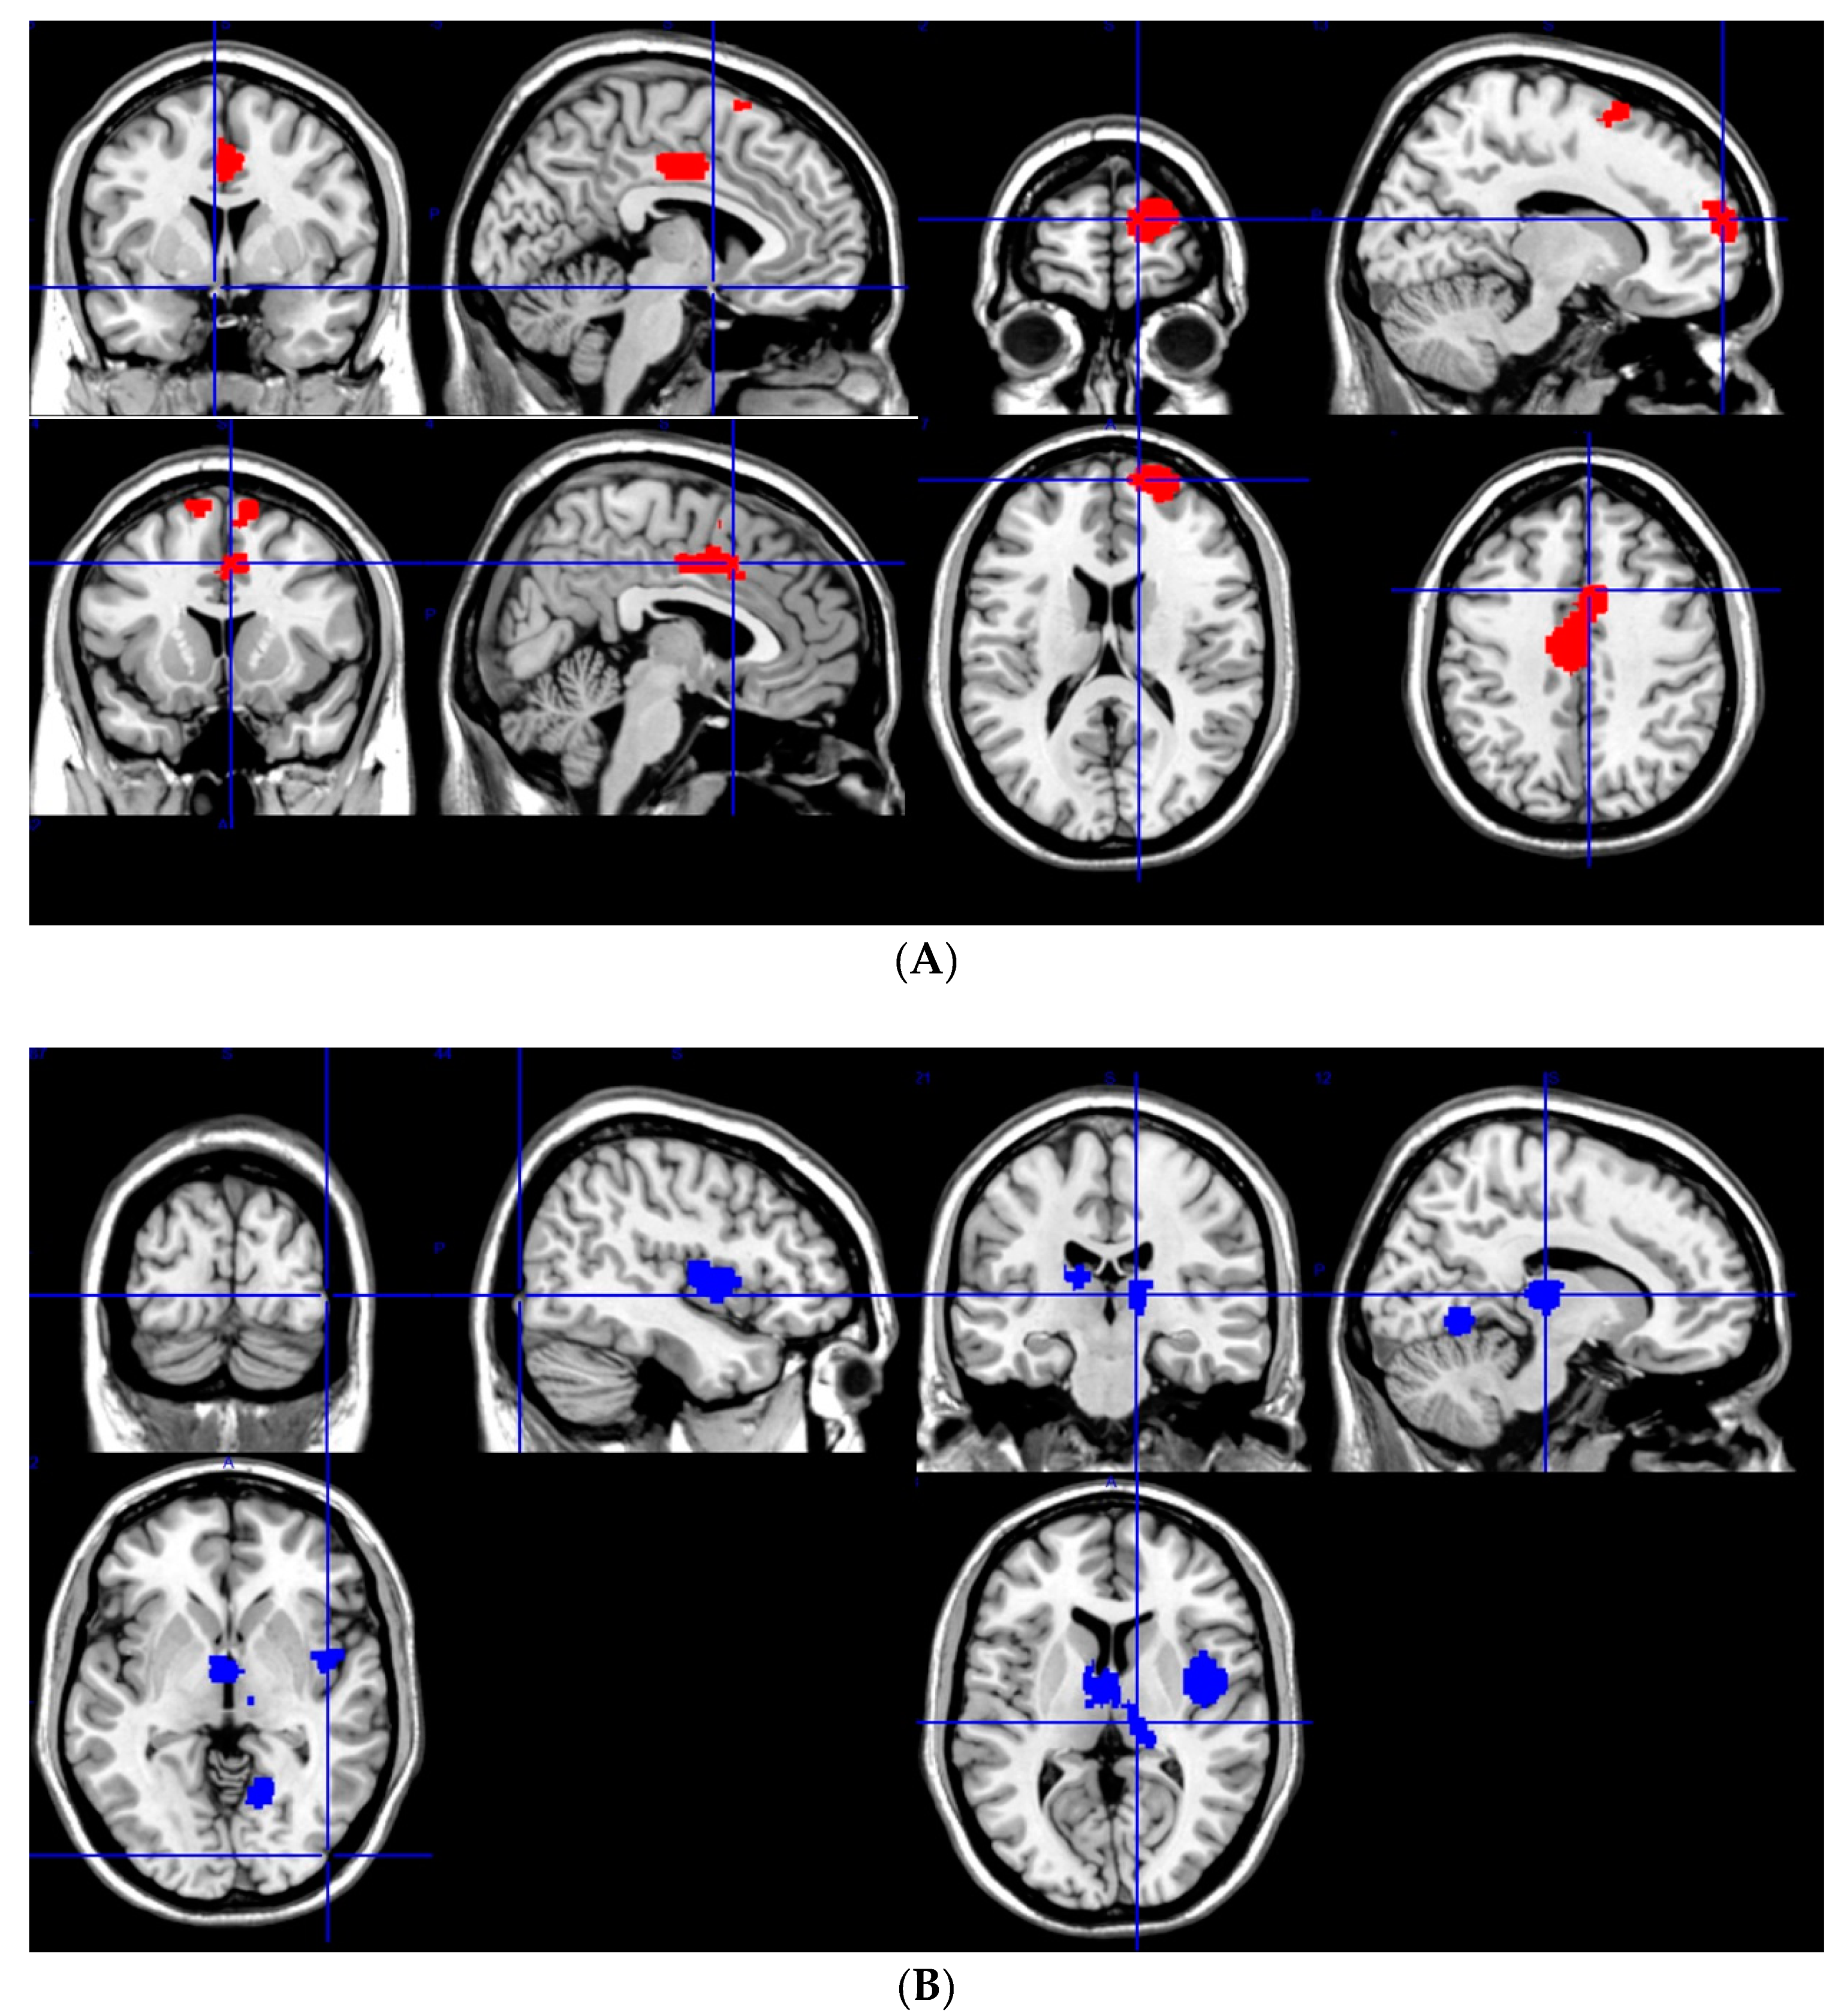

3.2. Gray Matter Changes in JME

3.2.1. GM Increases

3.2.2. GM Decreases